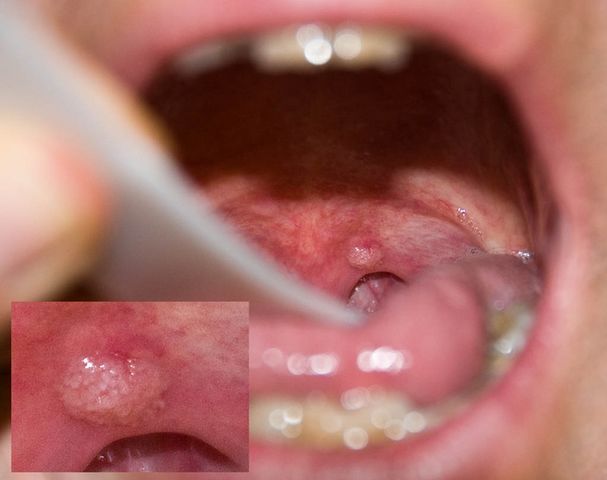

JFC Papiloma amigdalar izquierdo

JFC. Papiloma velofaríngeo.